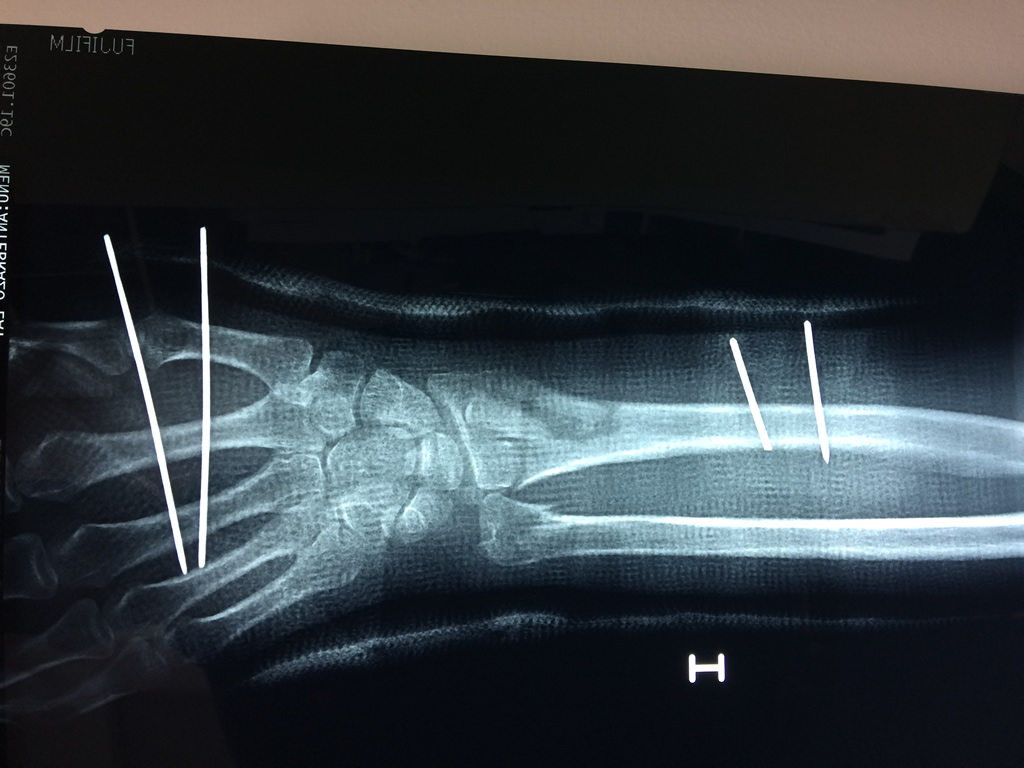

Calcaneo - Cirugías de Muñecas y Manos

Los procedimientos más comunes en cirugía de la mano son aquellos destinados a reparar traumatismos, incluyendo lesiones de tendones, nervios, vasos sanguíneos, y articulaciones; huesos fracturados; y quemaduras, cortes, y otros daños de la piel.